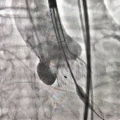

造影确定瓣膜形态

第二次瓣膜释放

瓣膜释放完毕

术后造影及超声探查未见瓣周漏,跨瓣压差术前44mmHg,术后几乎无压差,术中及术后未出现相关并发症,手术圆满完成。

孔令文教授熟练运用VenusA-Plus的可回收功能,稳定回收了第一次释放较深的瓣膜,通过细调胶囊腔位置,第二次就将瓣膜精确地释放在最佳工作位置,保证了患者最大的手术收益,同时VenusA-Plus可回收输送系统在多次回收释放后,没有出现支架打折、胶囊腔变形的情况,进一步证实了VenusA-Plus可回收输送系统面对复杂情况时依然能够保持产品的稳定性,为术者挑战高难度病例提供了有力保障。